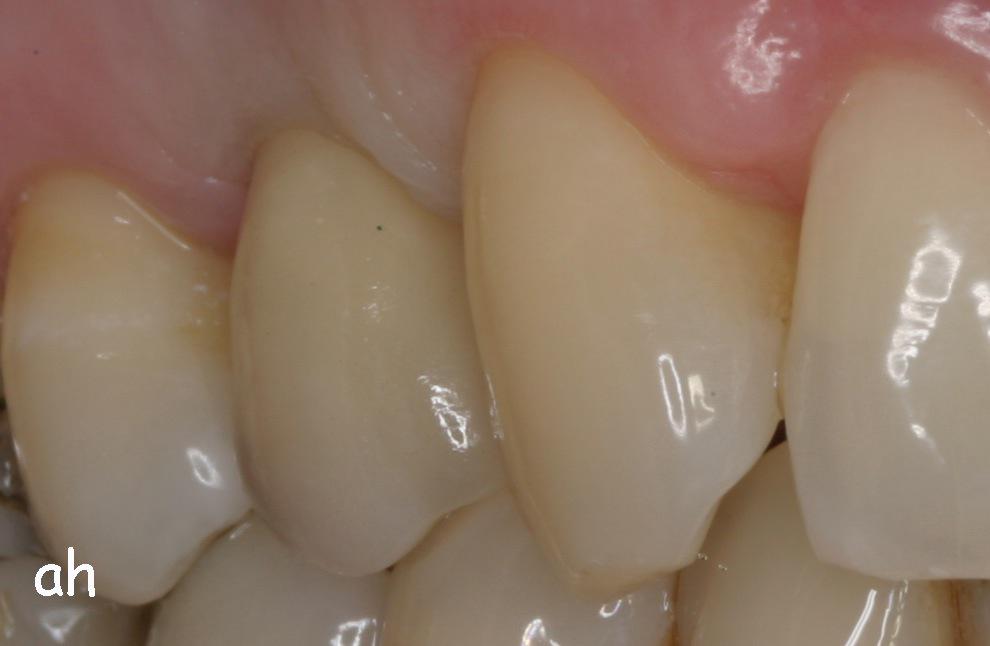

Exemple 1: Ce patient a perdu son incisive centrale gauche lors d'un accident. Un implant a été posé

Exemple 1: L'implant remplace la racine de la dent manquante

Exemple 1: L'implant s'est intégré dans l'os, une empreinte est effectuée. Le laboratoire peut réaliser la couronne en céramique.

Exemple 1: résultat final.